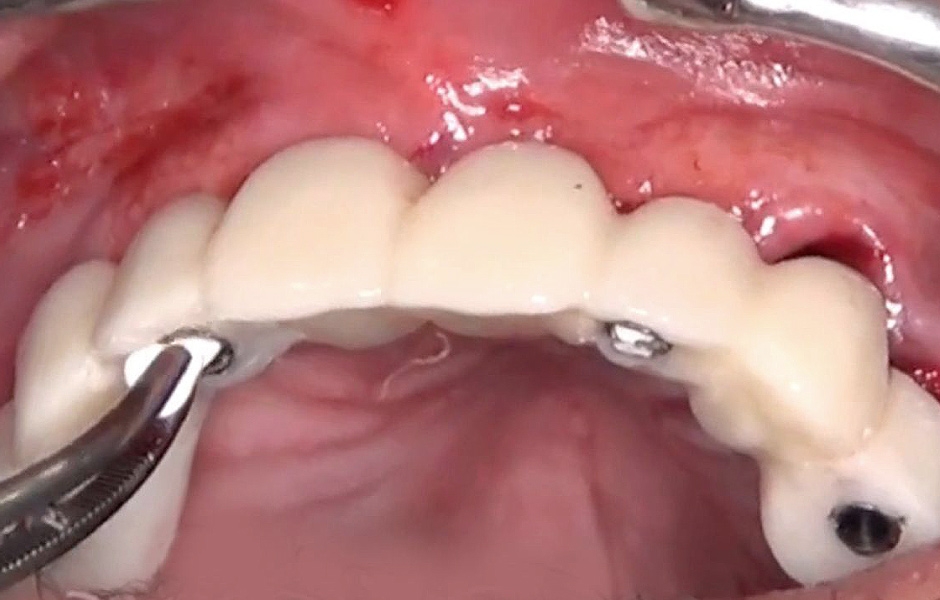

Byl zvolen protokol okamžitého zatížení implantátů s rovnoměrným rozložením sil na celou provizorní náhradu kotvenou dočasnými abutmenty. Prostory mezi abutmenty a provizorní náhradou byly vyplněny (obr. 36–38). Nadbytečný materiál byl odstraněn a provizorní náhrada byla následně vyleštěna, aby byl zajištěn hladký povrch (obr. 39). Pacient obdržel šroubovanou provizorní náhradu v den zavedení implantátů, která byla bezpečně přišroubována k titanovým abutmentům točivým momentem 15 Ncm (obr. 40). Byla zkontrolována okluze (obr. 41, 42). Následně byly pacientovi poskytnuty instrukce pro ústní hygienu.

Během kontrolních návštěv pacient vykazoval výborné hojení bez pooperačních komplikací. Provizorní náhrada poskytovala optimální stabilitu a přesnost dosedu, což přispělo ke komfortu a funkčnosti provizorního protetického ošetření (obr. 44).

Obr. 40

Obr. 44